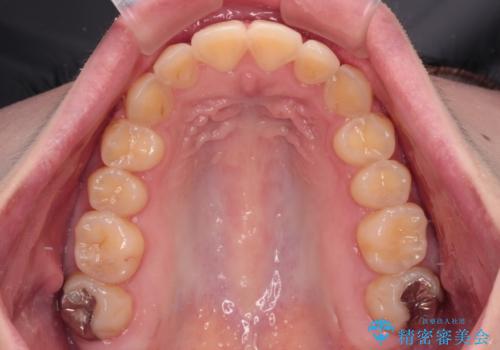

- 前歯のデコボコとクロスバイトが気になり、インビザラインによる矯正治療を希望して来院された患者様です。

上顎側切歯(上の真ん中から2番目の歯)が舌側転位している場合、無理して動かそうとすると歯髄壊死を起こすリスクが高い印象があります。

インビザライン単体でも治療は可能ですが、安全策としてインビザラインで歯列を移動する前に上顎前歯をワイヤー矯正で整え、その後上下歯列をインビザラインにて矯正治療を行うこととしました。

舌側転位している側切歯特有の、切縁の位置が不揃いであったり、根元が内側に引っ込んだ状態であったりという、インビザライン独特の仕上がりになることなく、きれいに整った歯列とすることができました。